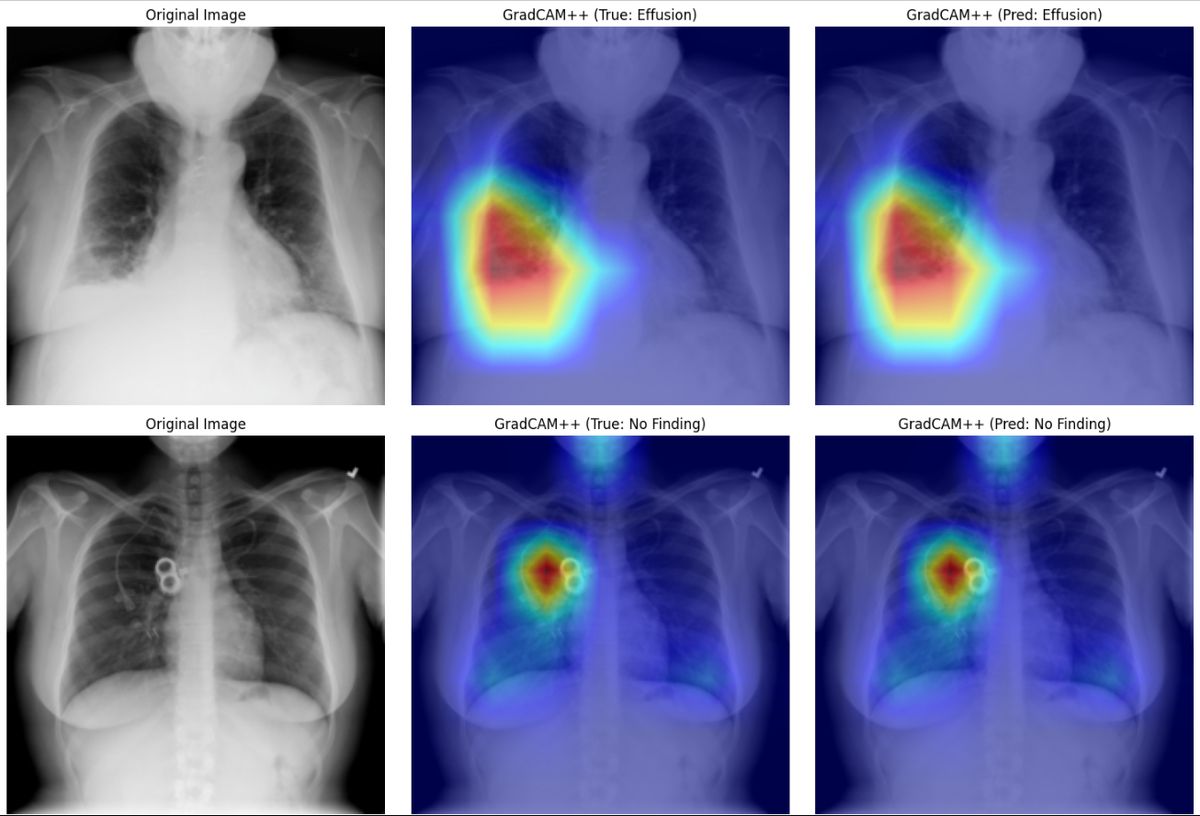

The AI Analysis module now demonstrates real GradCAM++ (Gradient-weighted Class Activation Mapping) performance — a technically sophisticated visualization method that highlights precisely which regions of a medical image the AI is using to form its conclusions. This is not a simulated output. It is a working computer vision system that interprets chest X-rays and other medical images with annotated accuracy. The AI now rapidly interprets uploaded scans, highlighting key findings, supporting diagnosis, and assisting radiologists with timely, accurate reporting.